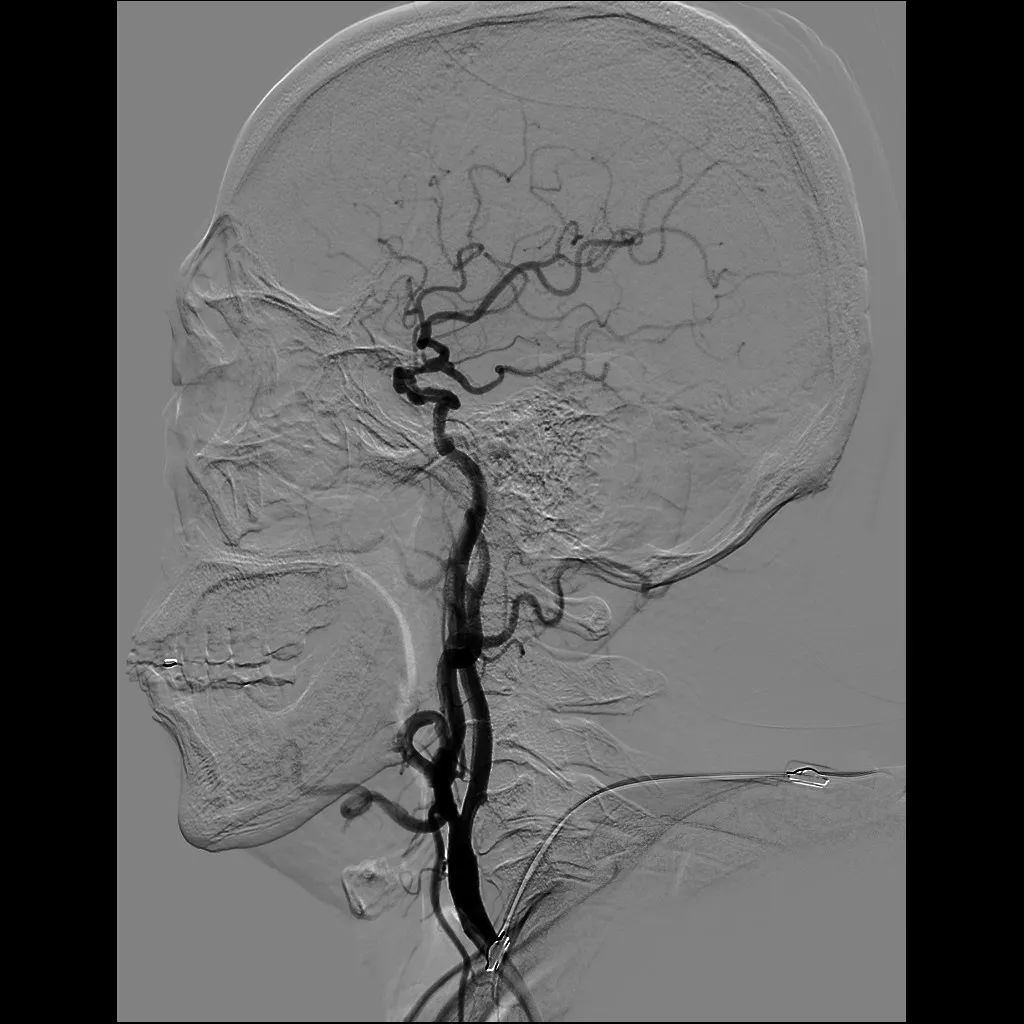

经过会诊讨论,神经内一科与心内科医师决定同时进行脑血管造影和冠状动脉血管造影,但由于两处造影所需手术器械不同,药物应用不同,为避免长时间手术,两科详细制定了手术方案,合理安排手术顺序,先进行脑血管造影术,后进行冠转动脉造影术,经过密切配合,仅用时40分钟就完成了造影。造影证实患者存在大脑中动脉狭窄和冠状动脉狭窄,但好在患者狭窄程度未达到支架植入的指征,继续抗血小板聚集、调脂稳斑等药物治疗,患者病情逐渐稳定并好转出院。